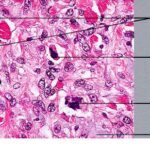

malignant-fibrous-histiocytoma